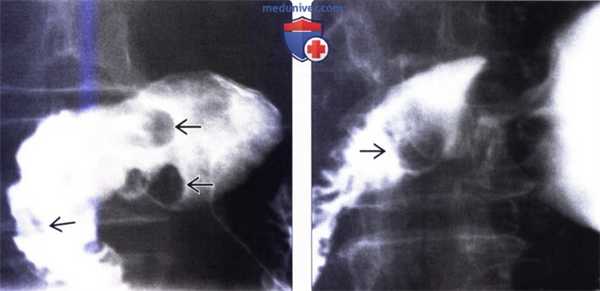

(Слева) На рентгенограмме, полученной при рентгеноскопии верхних отделов ЖКТ, визуализируются множественные мелкие подслизистые дефекты наполнения в луковице двенадцатиперстной кишки - изменения, характерные для гиперплазии бруннеровых желез.

(Справа) На рентгенограмме (кадр из рентгеноскопического исследования верхних отделов ЖКТ) визуализируется луковица двенадцатиперстной кишки, имеющая вид «клубники» вследствие наличия множественных мелких узелков в подслизистой оболочке, представляющих собой гиперпластические бруннеровы железы. (Слева) На рентгенограмме визуализируются множественные маленькие полиповидные образования в проксимальных отделах двенадцатиперстной кишки. При исследовании биоптата, полученного при эндоскопическом исследовании, были обнаружены признаки гиперплазии, а также выявлены элементы гамартомы, возникшей из Бруннеровых желез.

(Справа) На рентгенограмме (кадр из рентгеноскопического исследования верхних отделов ЖКТ) визуализируется луковица двенадцатиперстной кишки, имеющая вид «клубники» вследствие наличия множественных мелких узелков в подслизистой оболочке, представляющих собой гиперпластические бруннеровы железы.